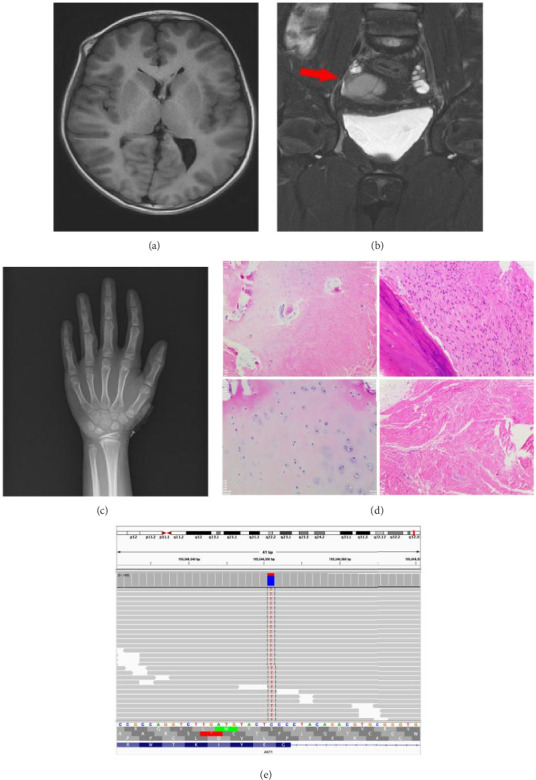

Proteus syndrome (PS) is an exceptionally rare disorder characterized by asymmetric and disproportionate overgrowth of connective tissues. We report the case of an 8-year-old female presenting with irregular cranial protrusion, bilateral supraorbital ridge enlargement, overgrowth of the right hand and left foot, and a pelvic MRI revealing an ovarian tumor. Initially, the patient was suspected of having Maffucci syndrome (MS) upon admission. Genetic analysis of a lesion sample from the fifth toe of the left foot identified a heterozygous point mutation, 49G > A (p.Glu17Lys), in the AKT1 gene. The patient met the clinical-molecular diagnostic criteria established by Leslie G. Biesecker, scoring 15 points, thereby confirming the diagnosis of AKT1-related PS. This case report contributes to the enhanced understanding of PS diagnosis associated with AKT1 mutations.